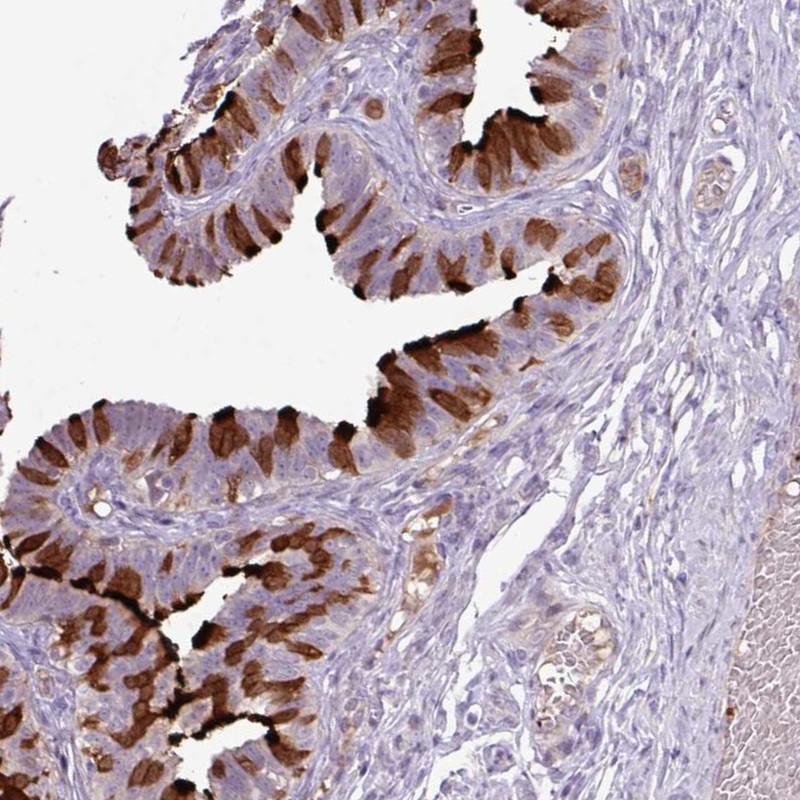

Immunohistochemistry analysis in human fallopian tube and tonsil tissues using Anti-DNAJB13 antibody. Corresponding DNAJB13 RNA-seq data are presented for the same tissues.